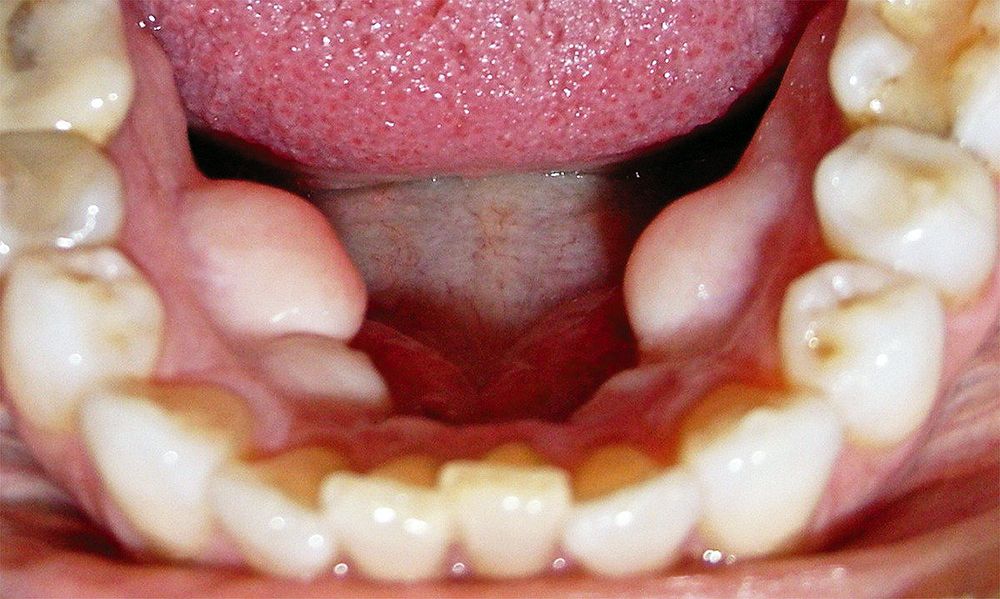

Son unas protuberancias que en el caso del maxilar superior suelen salir en la linea centrales del paladar.

En el caso de la mandíbula están por dentro, es decir por la parte lingual.